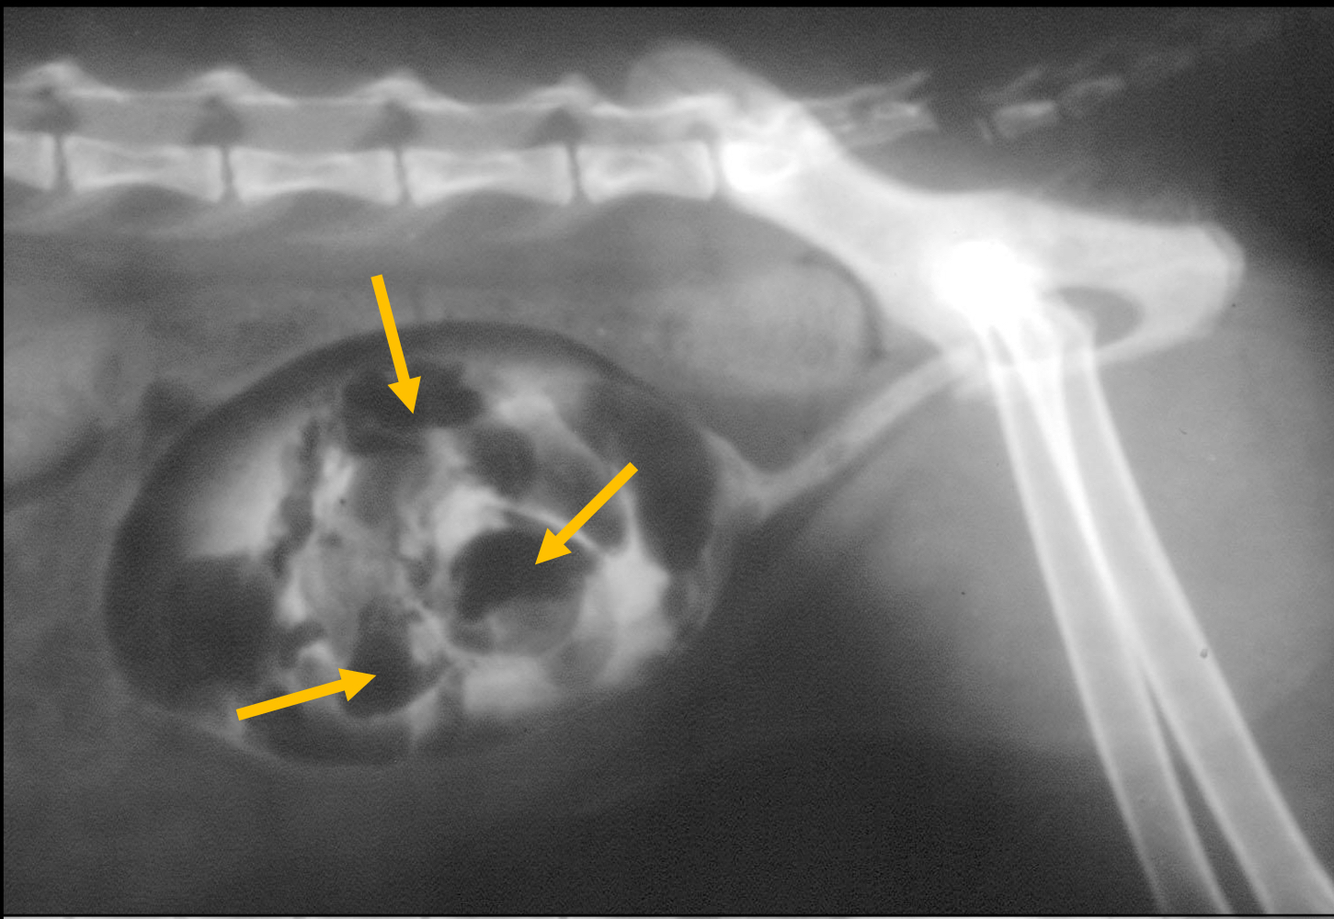

Q

• filling defect at trigone, common spot for TCC

• wall thickening